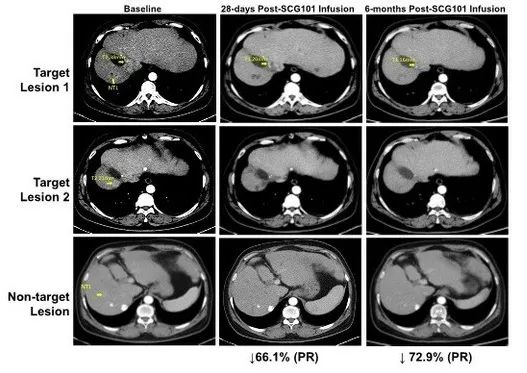

一项关于“SCG101治疗乙型肝炎病毒(HBV)相关肝细胞癌(HCC)”的临床研究,共纳入1例HBV相关的肝细胞癌患者,入组后仅接受单剂SCG101输注,而未接受其他抗肿瘤治疗,结果显示如下:

1、肿瘤缓解:患者在治疗第28天,达到部分缓解(PR),肿瘤靶病灶相比基线缩小66%,并在治疗第4个月进一步缩小至74.5%;同时另一处病灶完全消失。截至数据统计时,该患者肿瘤未进展时间已超过6.9个月。

图2 HBV相关肝细胞癌患者,回输SCG101前后影像学变化

2、HBV感染缓解:该患者在回输SCG101前后,肝脏免疫组化结果显示,乙肝表面抗原阳性肝细胞达到100%清除;HBsAg(HBV血清学标志)水平,也从治疗前的557.96 IU/mL,下降至1.3 IU/mL(回输SCG101第7天)、0.08 IU/mL(回输第28天)。